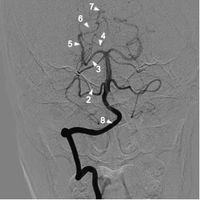

椎動脈正位2

椎動脈正位11 小腦後下動脈 2 小腦前下動脈

3 小腦上動脈 4 大腦後動脈P1段

5 大腦後動脈P2段 6 大腦後動脈P3段

7 大腦後動脈P4段 8 椎動脈

9 基底動脈

椎動脈多數起源於鎖骨下動脈,兩側椎動脈的管徑可以變化很大,一般情況下左側椎動脈管徑大於右側椎動脈管徑,但約1/4的正常人右椎動脈管徑大於左側椎動脈管徑。

小腦後下動脈是椎動脈入顱後發出的最重要的分支,在側位上顯示最清楚,分為4段2個袢。第1段也稱延髓前段,在延髓池內走行並從橄欖體下方繞過;第2段也稱延髓外段,在小腦延髓裂內走行,並形成尾側袢;第3段也稱延髓後段,為小腦後下動脈達到延髓後緣並在後髓帆後的上升部;第4段也稱扁桃體上段,為小腦後下動脈在扁桃體上方行走時形成的第二袢即頭側袢。小腦前下動脈和小腦後下動脈共乾是一種較常見的變異,有時一乾同時供應雙側小腦後下動脈也屬正常變異,個別情況下,椎動脈的終支延續為小腦後下動脈,此時後循環的血供主要依靠對側椎動脈。

基底動脈是由兩側椎動脈匯合而成,在正位片上位於中線或旁正中。基底動脈自橋延溝附近的起點到終端分為雙側大腦後動脈止,全長約32mm,平均管徑約3-4mm。分支主要有:從近端向遠端依次為小腦前下動脈、腦橋支、小腦上動脈、大腦後動脈。

大腦後動脈是基底動脈的終末。分為4段,P1段為交通前段(中腦段),為從基底動脈分叉至與後交通動脈匯合處;P2段為環池段,為從與後交通動脈匯合處至中腦後方這段距離;P3段為四疊體段,從中腦後方到距狀裂;P4段為距裂段,此段為大腦後動脈在距狀裂內的終末支。P1段在頦頂位或Towne位顯示最好,兩側P1段多不對稱,側位上P1段因從中腦前走向外側不易顯示。而P2段在側位上顯示清楚,常有一輕度向下的彎曲。兩側大腦後動脈在正位像上顯示在中腦後方彎曲向上彼此接近,標誌P3段的開始。P3段自中腦背側水平至距狀裂前僅數毫米,在Towne位或頦頂位顯示最好。P4段在正位顯示也很清楚。